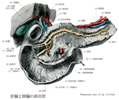

人体局所解剖図譜 II巻

Rauber Kopsch

Band2(079)